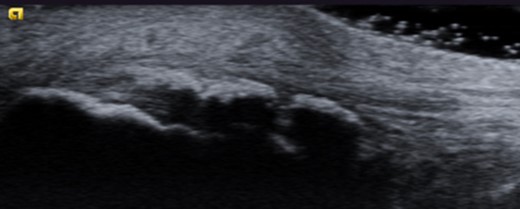

Dynamic ultrasound examination of the left heel showed a diffusely thickened subcutaneous bursa, with fluid-rich islands. Regions of high blood flow were seen in the bursal walls. There was tendinopathy in the distal Achilles, which measured 6–7 mm in thickness with intra-tendinous bone formations and calcification, but no high blood flow. Finally, there was a minor Haglund-like deformity with a sharp edge and a slightly enlarged retrocalcaneal bursa with the appearances of scar tissue formation, but no fluid or increased blood flow. There were no signs of partial ruptures in the distal part of the Achilles. These ultrasound findings were consistent with those of a previous MRI (Figs 1–5).

Ultrasound image of thickened subcutaneous bursa and bone formations in the distal Achilles.